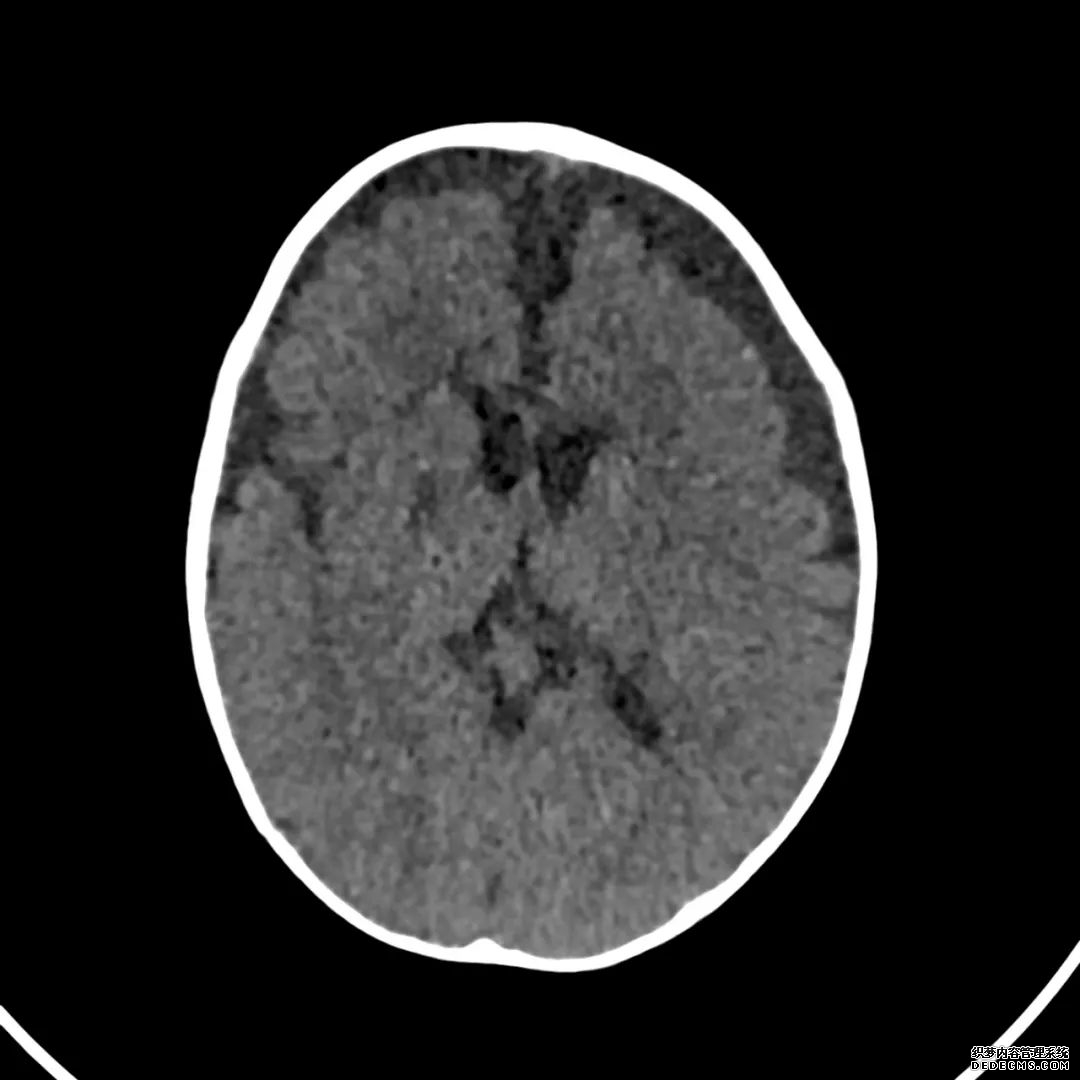

脑部CT检查显示扁豆状核内有略对称的低密度区。

脑MRI显示尾状核、扁豆状核和脑梗头部T2/FLAIR呈双侧对称异常高信号。扩散限制涉及这些区域,其特征是扩散加权DWI(B-1000)上的高强度,ADC图上相应的减弱强度。

印象:通过将这些成像模式与临床和实验室检查结果相结合,就有可能得出低血糖性脑病。